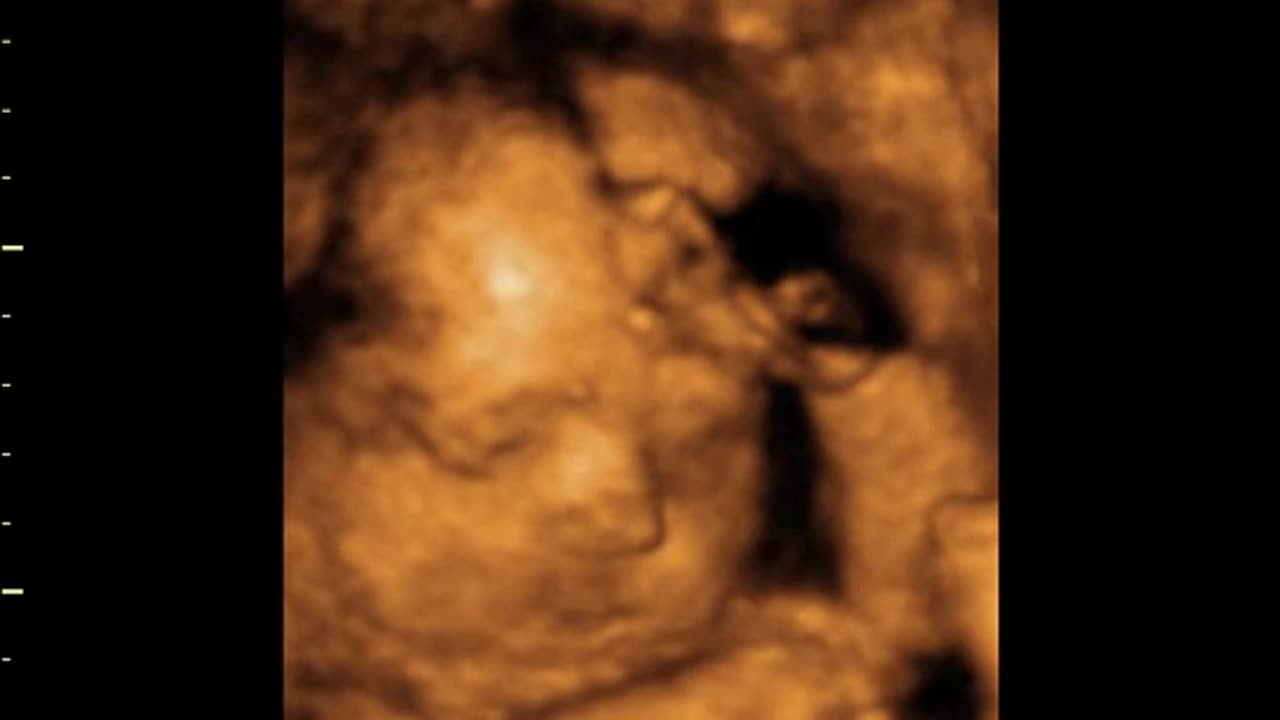

Liz - First View